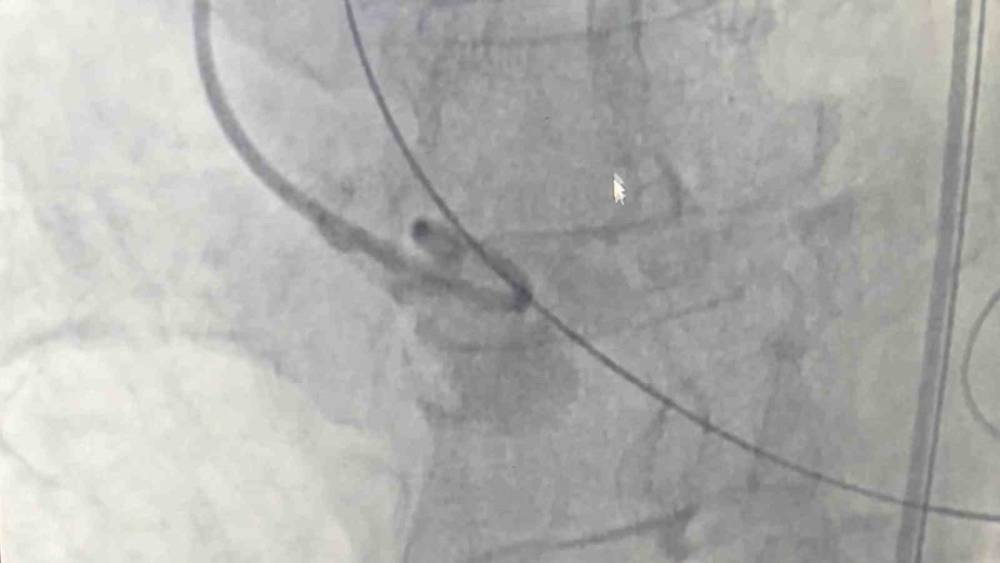

Samsun Eğitim ve Araştırma Hastanesi’nde 80 yaşındaki bir hastaya, nadir görülen dört yaprakçıklı aort kapağı nedeniyle transkateter aort kapak implantasyonu (TAVİ) yöntemiyle başarılı bir operasyon gerçekleştirildi. Operasyon, bu özelliği taşıyan vakalar arasında dünyada 18’inci, Türkiye’de ise ilk olma özelliği taşıyor. Amasya’nın Merzifon ilçesinde yaşayan Muzaffer Uslu (80), göğüs sıkışması ve baygınlık şikayetleriyle başvurduğu Merzifon Devlet Hastanesi’nden Samsun Eğitim ve Araştırma Hastanesi’ne sevk edildi. Tetkikler sonucu, normalde üç yaprakçıklı olması gereken aort kapağının dört yaprakçıklı olduğu belirlendi. Samsun Üniversitesi Tıp Fakültesi Kardiyoloji Ana Bilim Dalı Öğretim Üyesi Doç. Dr. Mustafa Yenerçağ, kapak değişiminin açık ameliyatla yüksek risk taşıması nedeniyle kapalı yöntem olan TAVİ işlemiyle çözüm sağladıklarını söyledi. "100 bin kişide 4 görülüyor" Doç. Dr. Yenerçağ, işlem öncesi yapılan tetkiklerde karşılaştıkları nadir bulgu hakkında ise "Hastanın TAVİ işleminden önce yapılan tetkiklerinde aort kapağının 3 yaprakçıklı olması beklenirken çok daha nadir görülen ‘Quadricuspid’ adı verilen 4 yaprakçıklı aort kapağı saptadık. Daha önce böyle bir vaka ile karşılaşmamıştık. Literatürleri, akademik çalışmaları inceledik. 4 yaprakçıklı aort kapağının toplumda 100 bin kişide 4 görüldüğünü, taradığımız uluslararası yayınlarda ise 4 yaprakçıklı aort kapağı bulunan sadece 17 hastaya TAVİ işlemi yapıldığını saptadık. Ülkemizden bildirilen vaka örneği bulamadık. Diğer ülkelerde yapılan vakaları detaylıca inceledik. İleri tomografik analizleri yaptık. Vakamıza detaylıca hazırlandık" dedi. 50 dakika içinde tamamlandı Operasyonu gerçekleştiren ekibi de paylaşan Yenerçağ, şunları söyledi: "Doç. Dr. Serkan Sivri, asistan doktorlarımız Berkan Öztürk ve Enes Kaya ile Anestezi Uzmanı Aynur Kaynar hocamızla beraber ekip halinde hastamıza başarılı TAVİ işlemini yaklaşık 50 dakika içerisinde tamamladık. Hastamızı 1 gün yoğun bakımda takip ettikten sonra servis takibine aldık. Nadir görülen bu 4 yaprakçıklı aort kapağına yaptığımız TAVİ işleminin prosedürel detaylarını literatüre kazandırmayı planlıyoruz. Bizden sonra bu nadir vaka ile karşılaşan meslektaşlarımıza yol göstermesi açısından referans olacaktır." Mustafa Uslu ise durumun iyi olduğunu söyledi.

Samsun Eğitim ve Araştırma Hastanesi’nde 80 yaşındaki bir hastaya, nadir görülen dört yaprakçıklı aort kapağı nedeniyle transkateter aort kapak implantasyonu (TAVİ) yöntemiyle başarılı bir operasyon gerçekleştirildi. Operasyon, bu özelliği taşıyan vakalar arasında dünyada 18’inci, Türkiye’de ise ilk olma özelliği taşıyor.

Amasya’nın Merzifon ilçesinde yaşayan Muzaffer Uslu (80), göğüs sıkışması ve baygınlık şikayetleriyle başvurduğu Merzifon Devlet Hastanesi’nden Samsun Eğitim ve Araştırma Hastanesi’ne sevk edildi. Tetkikler sonucu, normalde üç yaprakçıklı olması gereken aort kapağının dört yaprakçıklı olduğu belirlendi. Samsun Üniversitesi Tıp Fakültesi Kardiyoloji Ana Bilim Dalı Öğretim Üyesi Doç. Dr. Mustafa Yenerçağ, kapak değişiminin açık ameliyatla yüksek risk taşıması nedeniyle kapalı yöntem olan TAVİ işlemiyle çözüm sağladıklarını söyledi.

Doç. Dr. Yenerçağ, işlem öncesi yapılan tetkiklerde karşılaştıkları nadir bulgu hakkında ise "Hastanın TAVİ işleminden önce yapılan tetkiklerinde aort kapağının 3 yaprakçıklı olması beklenirken çok daha nadir görülen ‘Quadricuspid’ adı verilen 4 yaprakçıklı aort kapağı saptadık. Daha önce böyle bir vaka ile karşılaşmamıştık. Literatürleri, akademik çalışmaları inceledik. 4 yaprakçıklı aort kapağının toplumda 100 bin kişide 4 görüldüğünü, taradığımız uluslararası yayınlarda ise 4 yaprakçıklı aort kapağı bulunan sadece 17 hastaya TAVİ işlemi yapıldığını saptadık. Ülkemizden bildirilen vaka örneği bulamadık. Diğer ülkelerde yapılan vakaları detaylıca inceledik. İleri tomografik analizleri yaptık. Vakamıza detaylıca hazırlandık" dedi.

Operasyonu gerçekleştiren ekibi de paylaşan Yenerçağ, şunları söyledi:

"Doç. Dr. Serkan Sivri, asistan doktorlarımız Berkan Öztürk ve Enes Kaya ile Anestezi Uzmanı Aynur Kaynar hocamızla beraber ekip halinde hastamıza başarılı TAVİ işlemini yaklaşık 50 dakika içerisinde tamamladık. Hastamızı 1 gün yoğun bakımda takip ettikten sonra servis takibine aldık. Nadir görülen bu 4 yaprakçıklı aort kapağına yaptığımız TAVİ işleminin prosedürel detaylarını literatüre kazandırmayı planlıyoruz. Bizden sonra bu nadir vaka ile karşılaşan meslektaşlarımıza yol göstermesi açısından referans olacaktır."